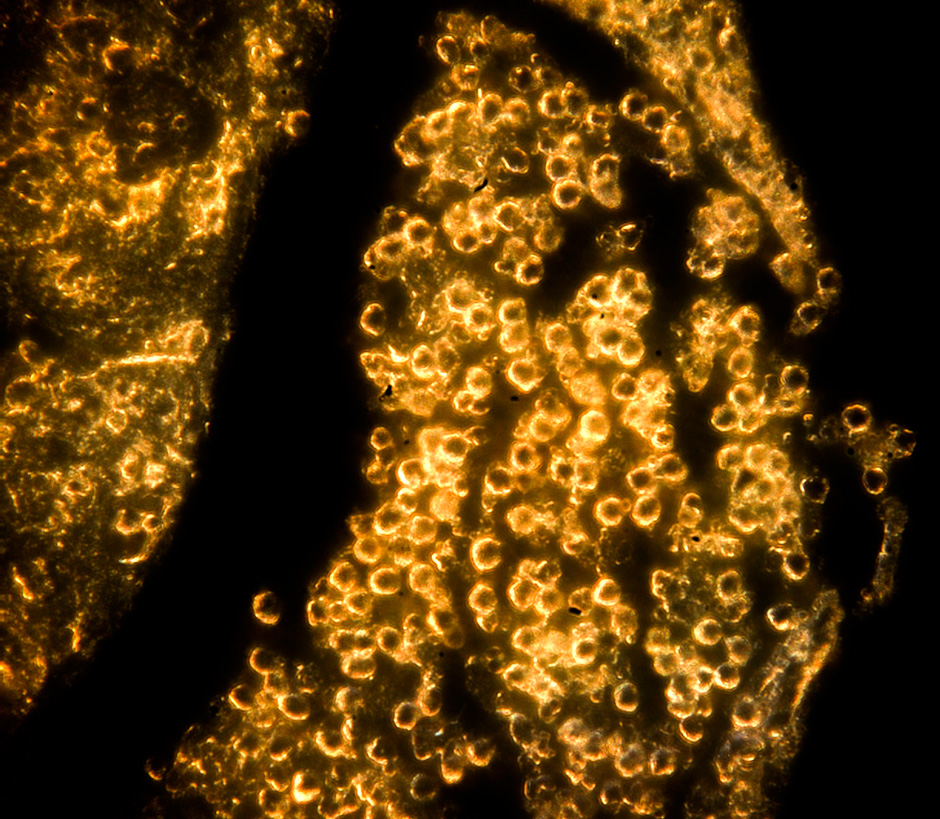

«Несмотря на длинный и немного пугающий названиями список компонентов, все они в высокой степени биосовместимы и активно используются в биомедицине, — пояснил один из соавторов работы, научный сотрудник лаборатории „Биомедицинские наноматериалы“ НИТУ „МИСиС“, PhD Роман Акасов. — Полученная смесь перемешивается под действием ультразвука, формируя двойную эмульсию вода-масло-вода. Дальше ее можно облучить ультрафиолетом, в результате чего в растворе происходит формирование наночастиц золота. При этом частицы окружены полимером, который придает им свойства биосовместимости и устойчивости в водных растворах. Эмульсия при этом превращается из беловато-прозрачной в красную, что является индикатором успешного проведения фотополимеризации. Размер частиц в наших экспериментах составлял около 100 нанометров, что привлекательно для биомедицинских применений, и частицы не были токсичны для клеток».

Также в работе авторам удалось показать, что золотые наночастицы накапливаются в цитоплазме клеток — как опухолевых глиомных, так и иммунных клетках макрофагах. Это открывает возможности индивидуальной диагностики и терапии опухолевых заболеваний. В дальнейшем планируется модифицировать поверхность наночастиц специальными молекулами, чтобы адресно находить опухоль в организме. Однако исследователи предлагают и другой вариант использования своего метода — как биоконструктор.